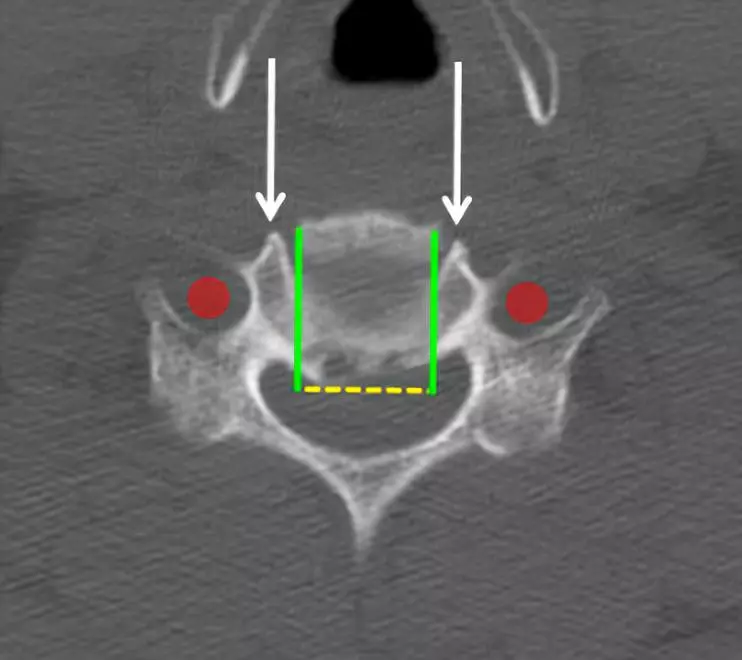

注意保持在横向的钩突关节(白色箭头)的边缘内。椎动脉(红色圆圈)位于其侧面外侧。

分离后纵韧带并切除。

可以在头端和尾端椎体后面轻轻地穿过神经探钩以确认脊髓减压充分。然后神经钩可以从椎间孔中穿出以确认神经根减压。